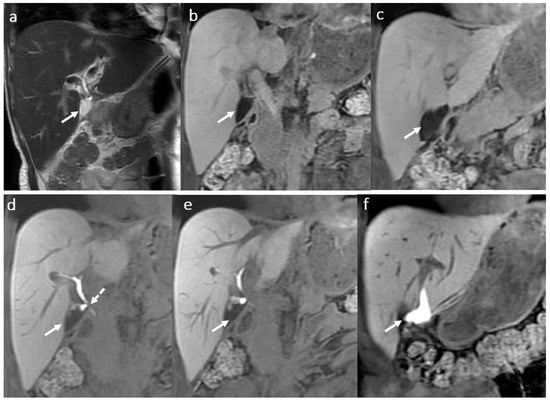

3.8. Primary Sclerosing Cholangitis

3.9. Other Changes